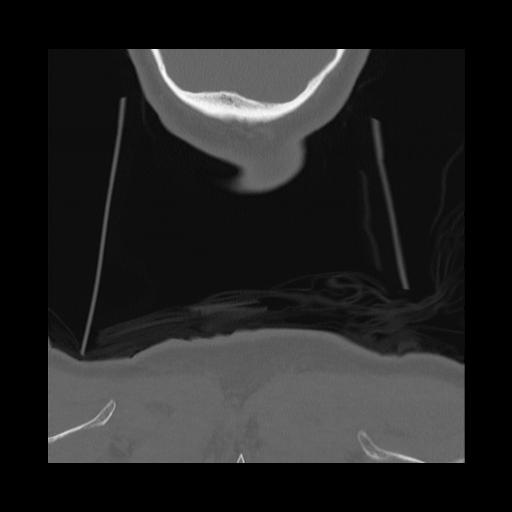

16 HUESO,,Coronal,2.000,HUESO,Coronal,